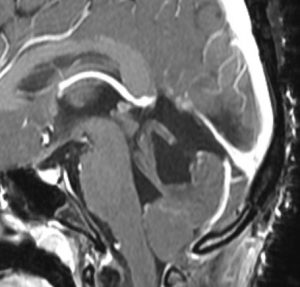

18歳で発症して,60歳まで無治療の大きな視床下部毛様細胞性星細胞腫

hypothalamic pilocytic astrocytoma

1968年 18歳の時に頭痛嘔吐で発症しました。第3脳室腫瘍と閉塞性水頭症の診断だけで,シャント手術を受けました。手術も化学療法も放射線治療もされていません。下の画像は60代で撮影されたものです。この例では,第3脳室内に増大した大きな毛様細胞性星細胞腫が,視床下部下垂体障害を出すことなく,自然経過で増大停止 growth arrest して,カチカチに固まってしまうということを教えてくれます。でも,こんなに都合よく経過観察できる例も珍しいです。

CTでは強い石灰化があります。右のT2強調画像では腫瘍は等信号,視交叉の後ろにあります。内部の低信号は石灰化です。

T1強調画像では等信号,ガドリニウム増強でごく一部がまだらに増強されます。